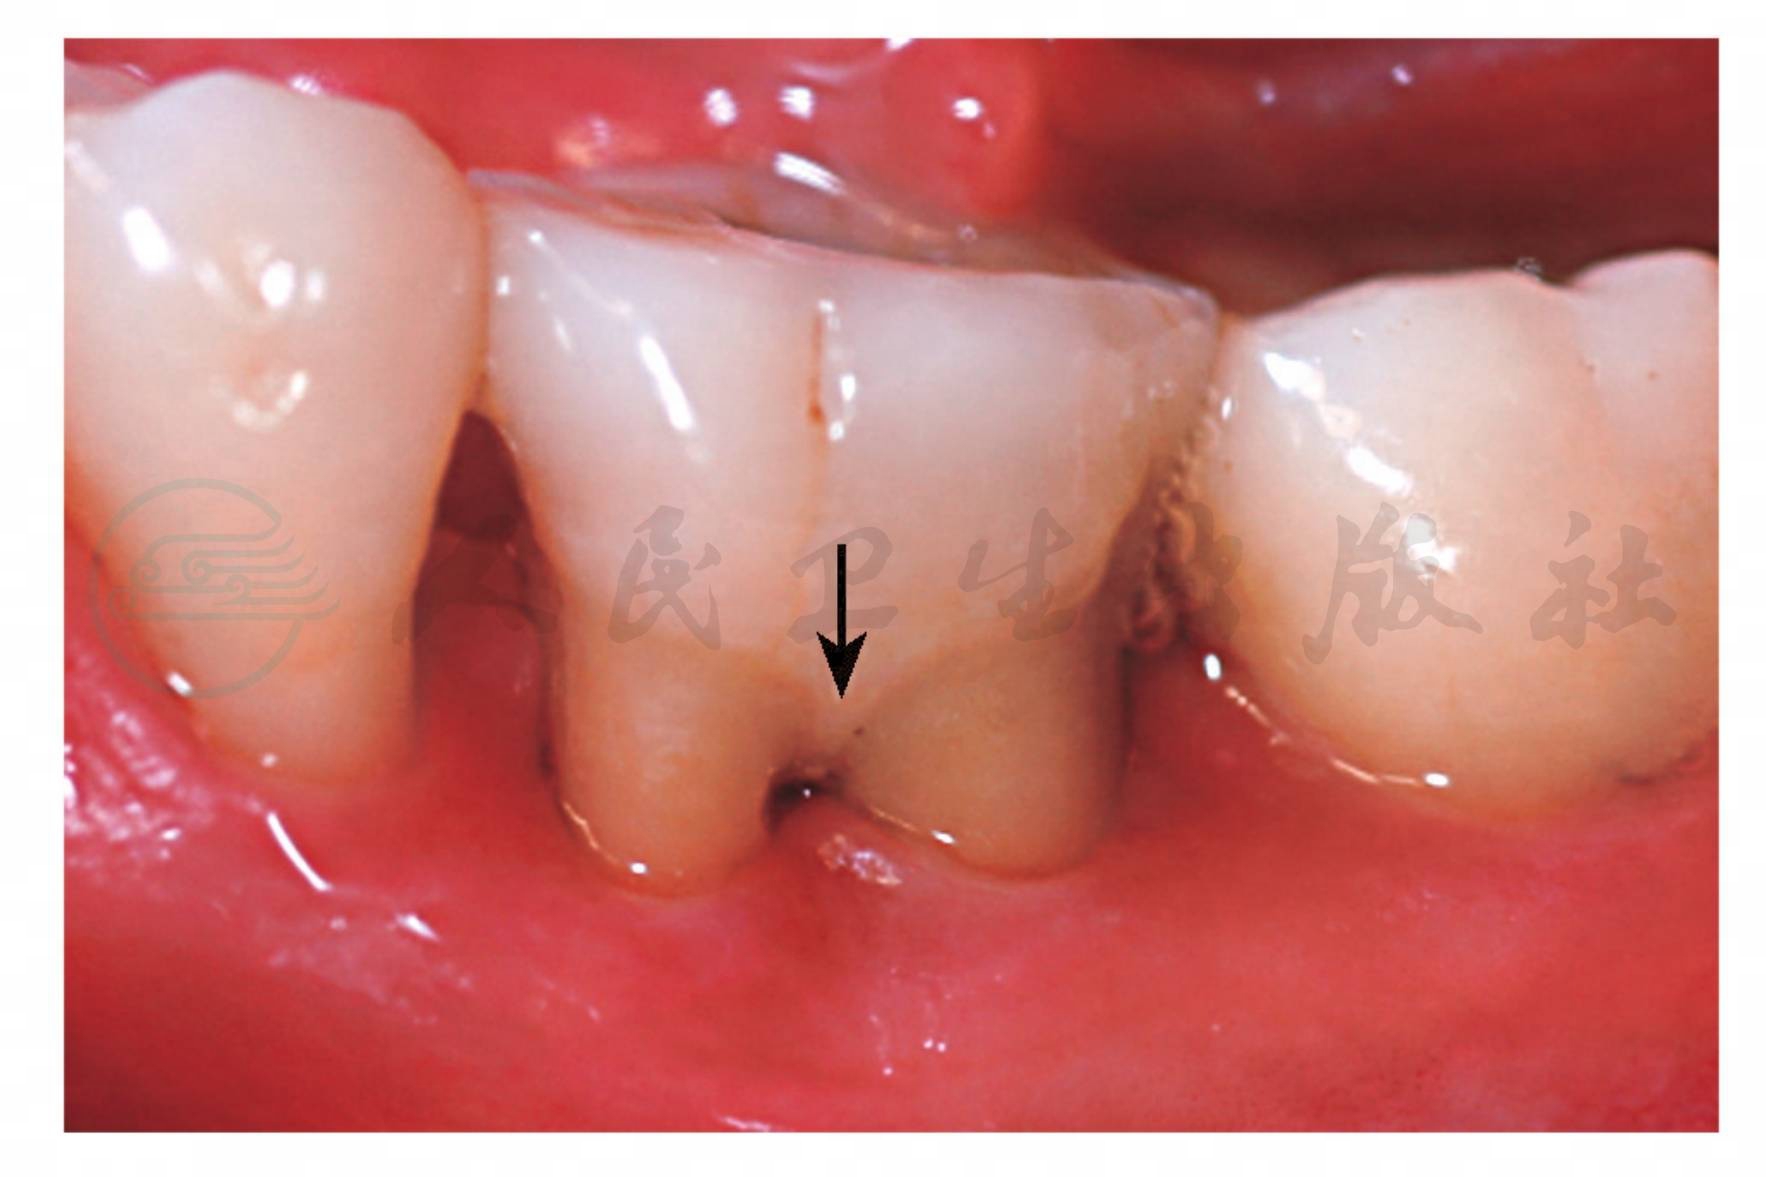

牙釉质在釉牙骨质界的根方异位沉积呈指状突起伸向根分叉处,有的突起还能进入根分叉区内,被称为“颈部釉突(cervical enamel projection)”(图1),是根分叉病变的发病因素。有学者采用探诊、拍根尖X线片、翻瓣等方法观察了78名有根分叉病变的患者,发现有釉突的牙容易发生根分叉区的牙周病变,患病率可达82.5%,因为该处结合上皮的附着易被破坏,而无颈部釉突的磨牙根分叉病变只有17.5%。

图1牙釉质突起深入到根分叉内